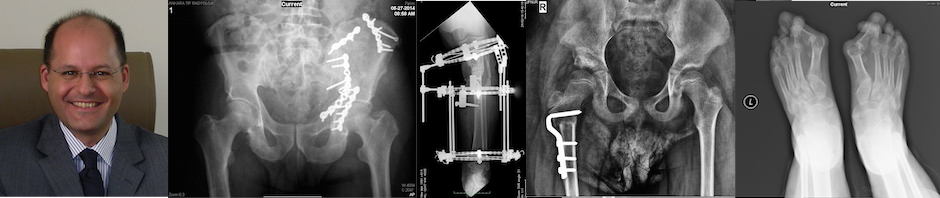

Prof. Dr. Hakan KINIK – Ortopedi ve Travmatoloji Uzmanı